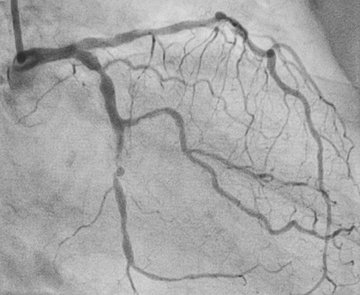

Ein verschlossenes Gefäß auf einem Röntgenbild